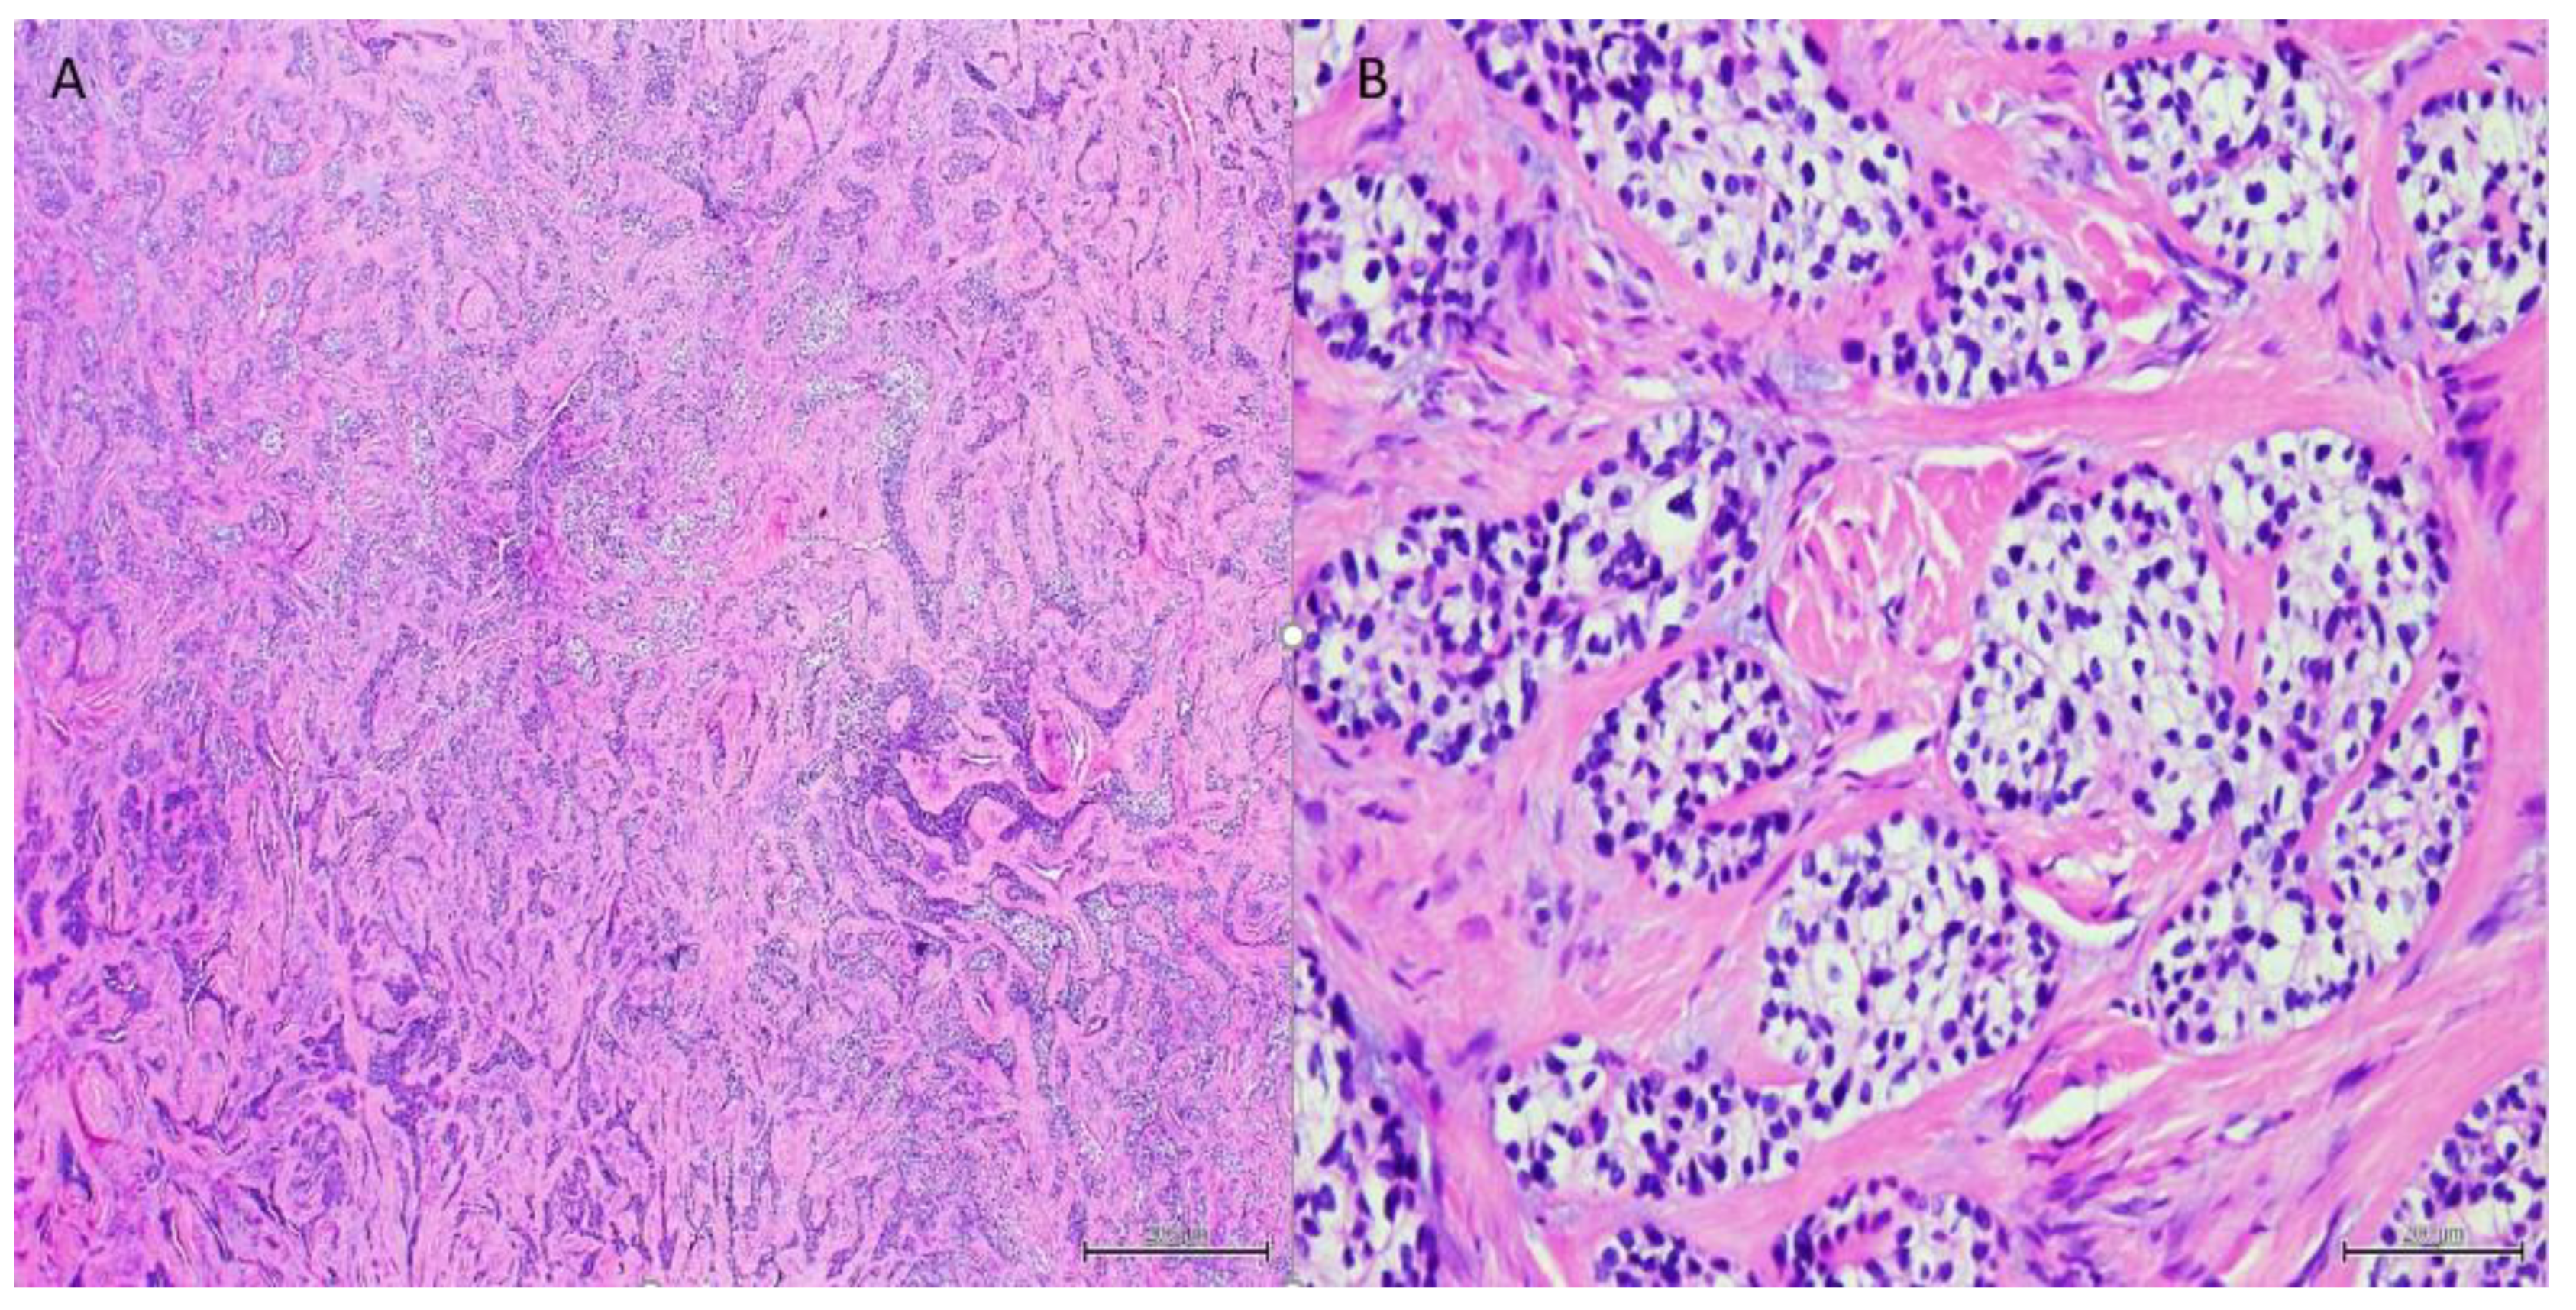

| Morphology | Infiltrative, non-encapsulated malignant neoplastic odontogenic epithelial proliferation with clear cell component in a dense fibrous connective tissue stroma. Neoplastic cells arranged in anastomosing trabeculae. Nuclear hyperchromasia and pleomorphism surrounded by clear, vacuolated cytoplasm. Stroma was hyalinized, densely collagenized, hypocellular, and hypovascular. | Neoplastic odontogenic epithelial proliferation diffusely infiltrated the connective tissue stroma. Neoplastic cells arranged in islands of variable size, trabeculae, and nests. Nuclei were hyperchromatic, central, and pleomorphic surrounded by clear cytoplasm. | Infiltrative odontogenic epithelial neoplasm intermixed with eosinophilic dentinoid matrix. Neoplastic cells arranged in infiltrative, non-encapsulated sheets, cords, and nests of polygonal cells with central hyperchromatic and slightly pleomorphic nuclei surrounded by clear cytoplasm and occasional pale eosinophilic cytoplasm. Occasional mitotic figures were noted. Neoplastic epithelial sheets and cords blended with eosinophilic cellular matrix without cellular rimming consistent with dentinoid deposits. |